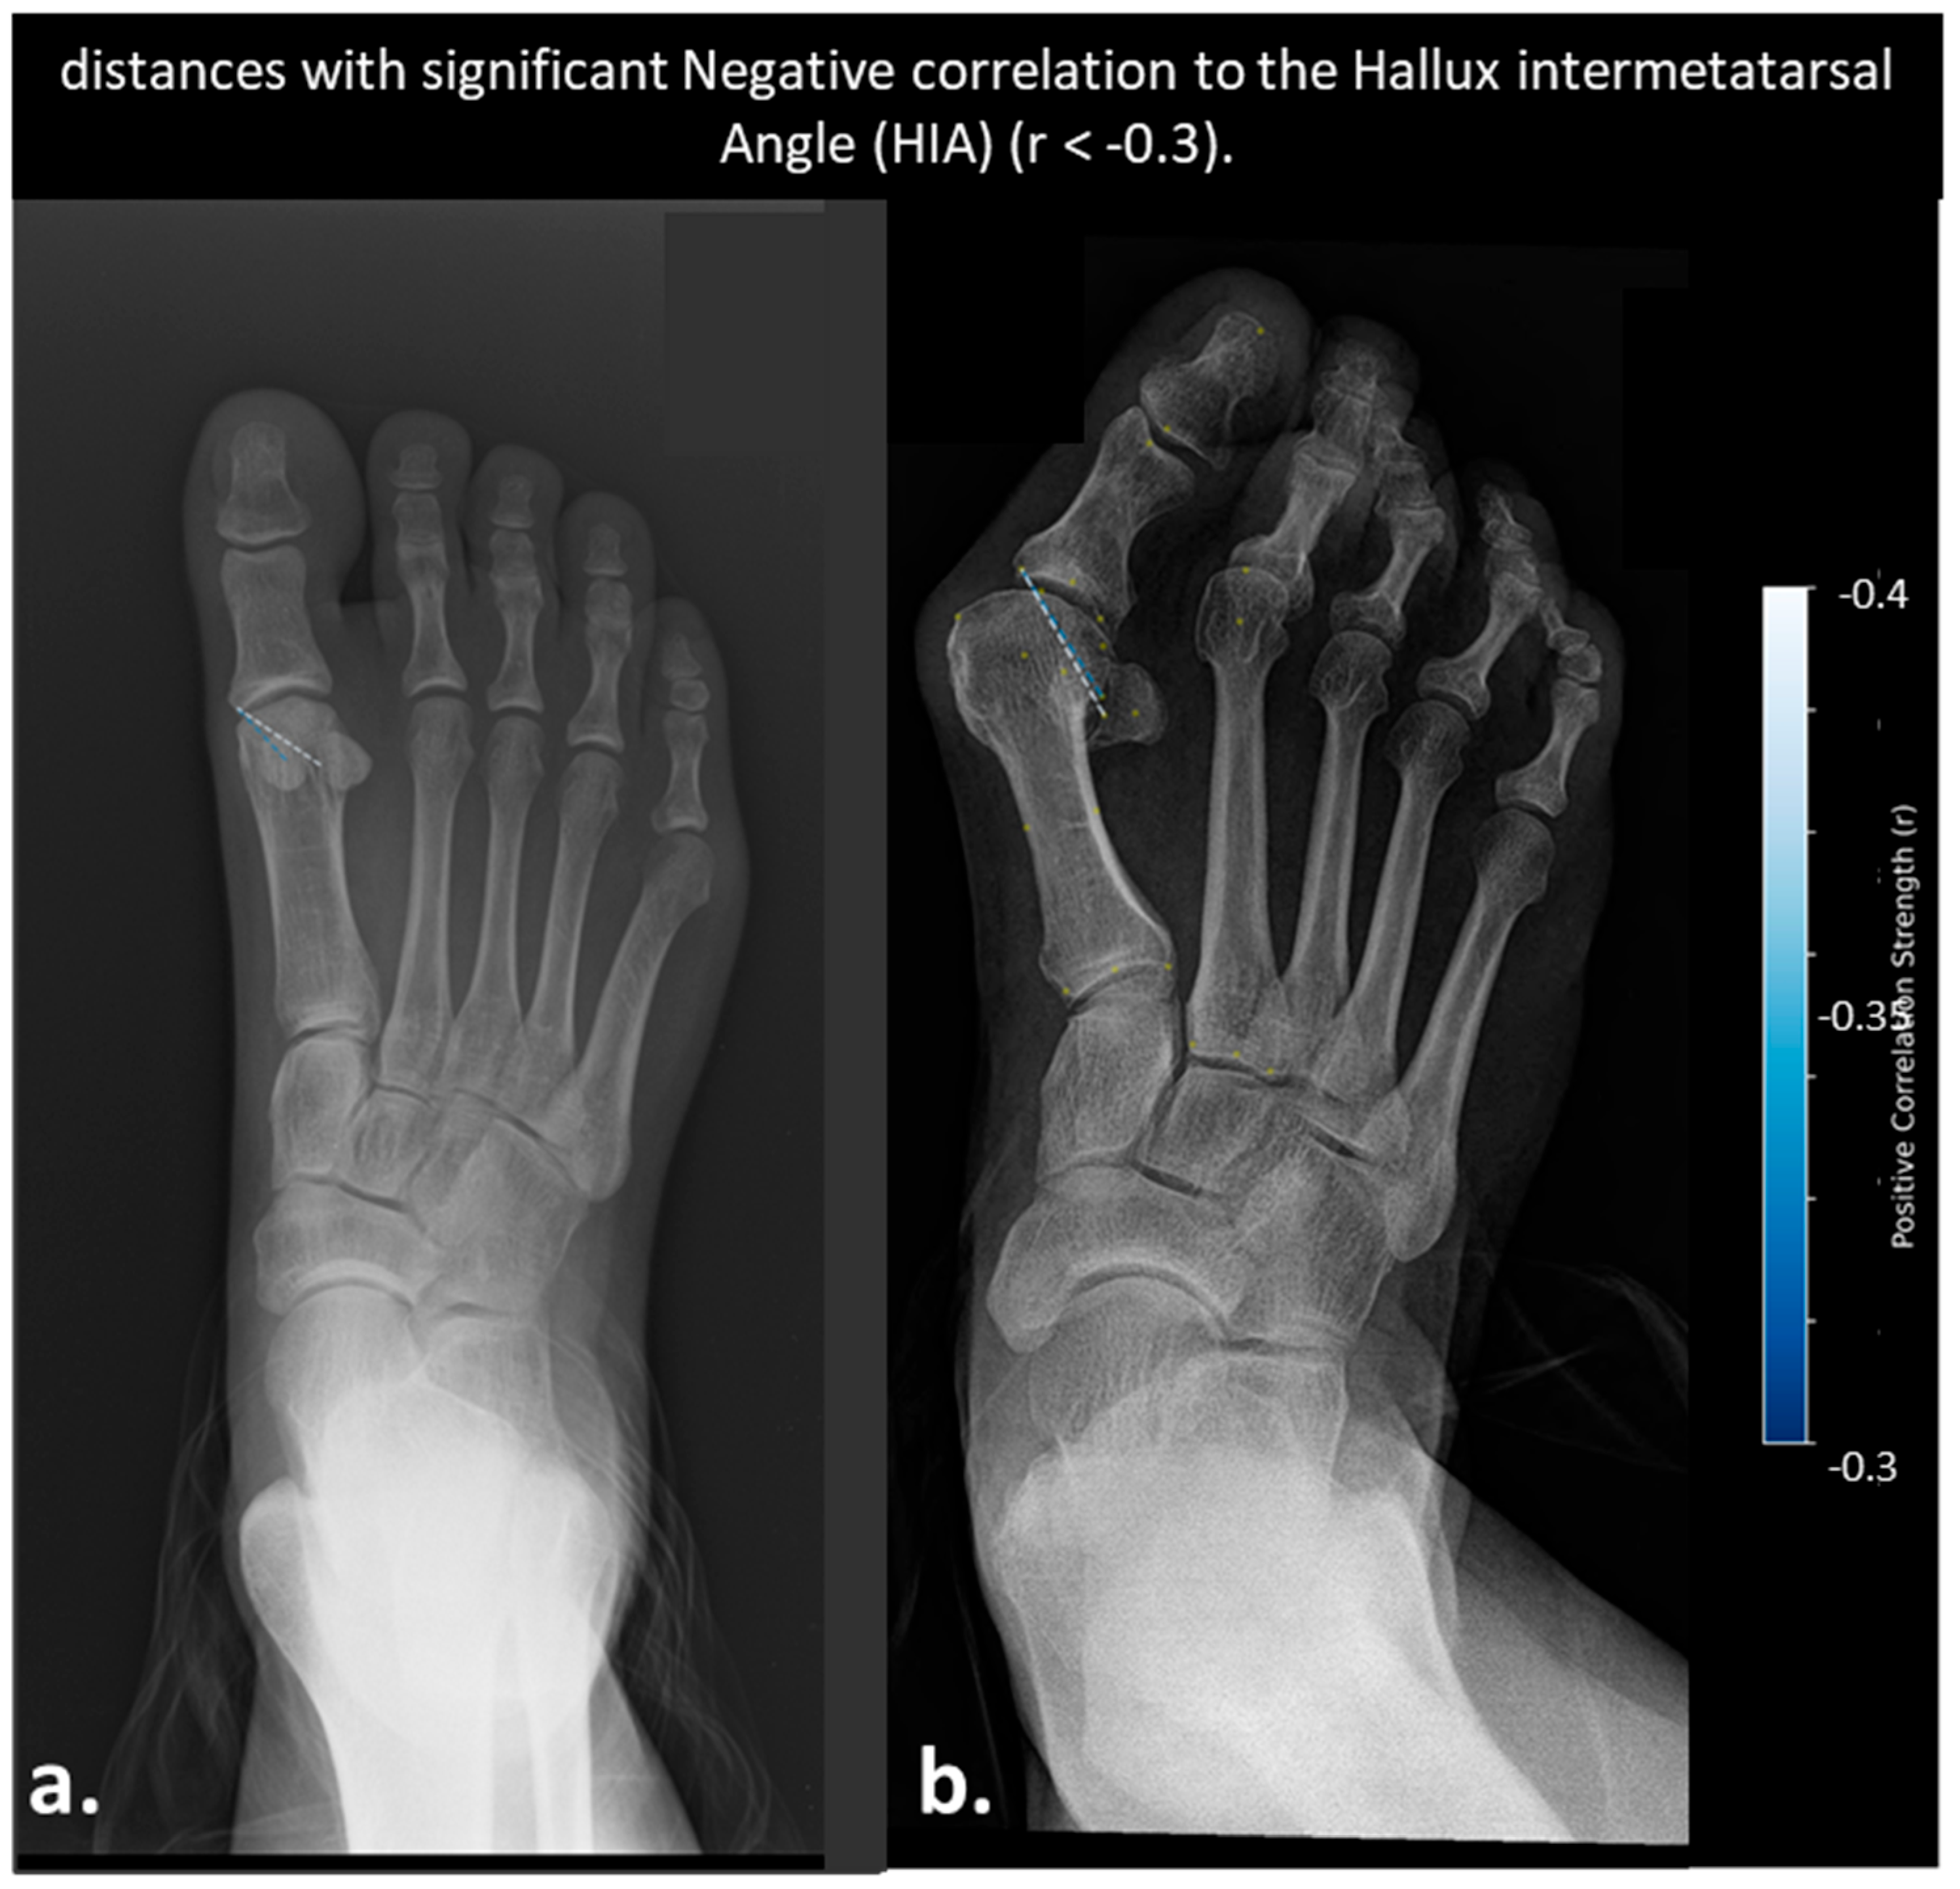

- Color Scale: The gradient ranges from dark blue (−0.6) to dark red (0.6), indicating the strength and direction of correlation (negative to positive).

- Correlation Coefficients: Values are color-coded, with significant correlations (p < 0.05) highlighted. Notable ranges include r > 0.4 for HVA and IMA, and r > 0.3 for DMAA and HIA.

- Annotations: Specific distances (e.g., “2nd metatarsal head to proximal phalanx head,” “Medial sesamoid to proximal phalanx base”) are labeled to reflect anatomical relationships.

- Distances Correlated with Hallux Interphalangeal Angle (HIA)